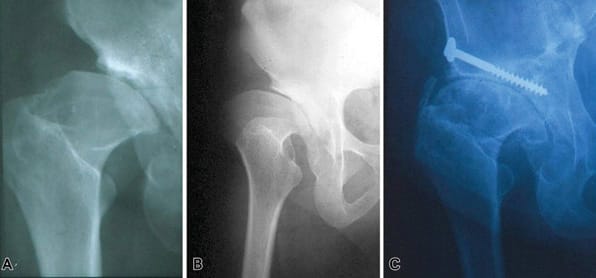

Bone block arthroplasty

First described by König in 1891, the bone block technique has been adapted and modified by countless authors with an arthroscopic technique recently presented [7], Chiron P, Laffosse JM, Bonnevialle N. Shelf arthroplasty by minimal invasive surgery: technique and results of 76 cases. Hip Int 2007;17 Suppl 5:S72-82. https://doi.org/10.5301/hip.2008.1488[8] Migaud H, Chantelot C, Giraud F, Fontaine C, Duquennoy A. Long-term survivorship of hip shelf arthroplasty and Chiari osteotomy in adults. Clin Orthop Relat Res. 2004 Jan;(418):81–6. https://doi.org/10.1097/00003086-200401000-00014. It involves grafting a fragment of cancellous-cortical bone to the anterosuperior part of the acetabulum to improve bone coverage.

In contrast to the PAO or RAO this strategy increases the size of the acetabulum, similarly to the Chiari osteotomy, which involves metaplasia of the of the capsule and labrum to create a fibrocartilaginous interposition graft.

There are countless options for the approach route, with Smith–Peterson typically being used, although the Hueter anterior approach, minimally invasive medial approach described by Chiron and the Thaunat arthroscopic approach are all possible. The bone graft is taken from the exopelvic part of the iliac crest, and its size is determined preoperatively based on the desired correction. An incision is made at the anterosuperior part of the acetabulum, flush with the capsule, so that the bone block can be placed against the capsule and is stable without fixation. The fragment is then impacted until it is fixed well and/or fixed with screws and/or a plate.

The main complications are lysis of the graft and non-union.

Results have been mixed with 46% survivorship without THA for Fawzy et al and 37% after 20 years in our facility. This is in contrast to Japanese studies with over 70% survivorship with 30 years of follow-up. These results are, however, difficult to compare to those of PAO or RAO because they are used in different populations. In the bone block studies, the largest portion of the population are patients with osteoarthritis, while the advent of modern pelvic osteotomies has been more recent, meaning patient selection has improved, and consequently so have the clinical results. If we look at bone block in the absence of osteoarthritis and subluxation, the survival rate is 81% after 21 years of follow-up [8] Migaud H, Chantelot C, Giraud F, Fontaine C, Duquennoy A. Long-term survivorship of hip shelf arthroplasty and Chiari osteotomy in adults. Clin Orthop Relat Res. 2004 Jan;(418):81–6. https://doi.org/10.1097/00003086-200401000-00014. However, this is a salvage strategy for extremely subluxed or even dislocated hips in which neither PAO nor RAO is possible, nor Chiari osteotomy in view of the risk of the line ending in the sacroiliac joint, preventing medialisation (Figure 6).